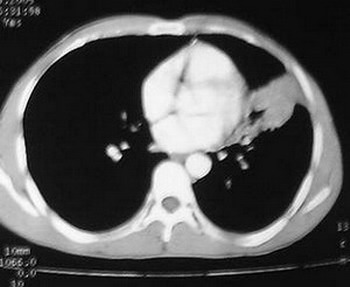

2.)纵膈窗片见:垂直胸膜边缘平直甚至微凹;

左肺舌叶大片影,支气管通入,但有纠集,边界不清,与侧壁胸膜广基相续,首先考虑感染性病变.血象与血沉及痰检.除外有结核可能

左上叶下舌段肺不张,无明显强化,上叶下舌段支气管开口区见不规则狭窄,并见小结结灶,首先考虑支气管内膜结核并舌段肺不张,炎性假瘤不排除.